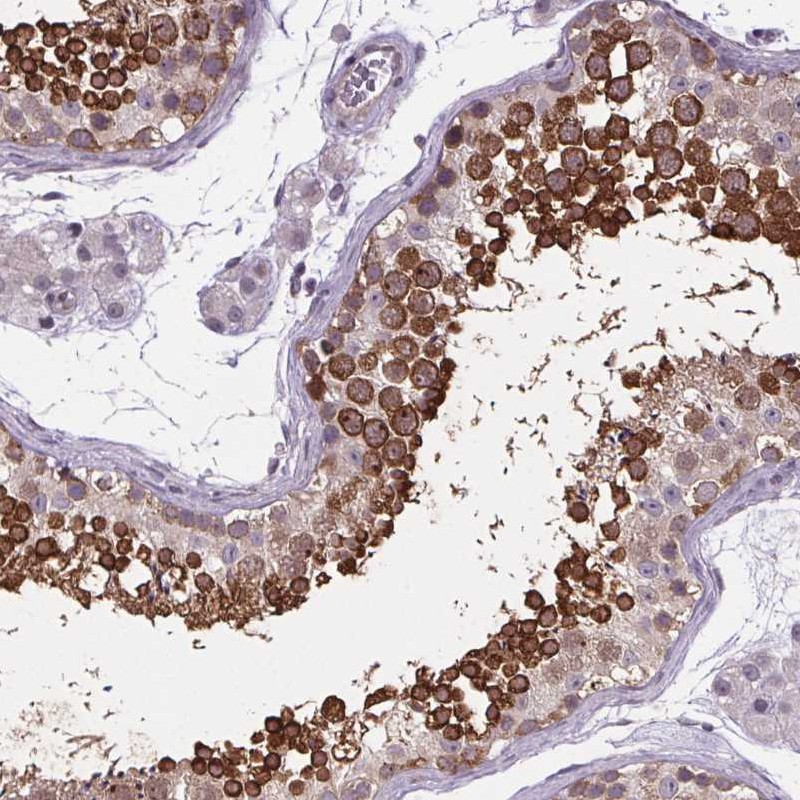

Immunohistochemical staining of human testis shows strong cytoplasmic positivity in cells in seminiferous ducts.